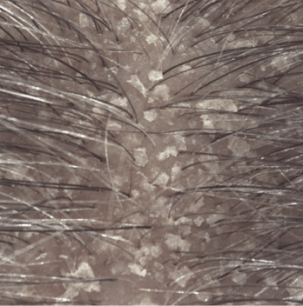

Le shampooing KERTYOL PSO est spécifiquement indiqué pour la prise en charge du psoriasis du cuir chevelu.

Actif kératolytique induisant une perte de cohésion significative au niveau du stratum corneum : desquamation des plaques épaisses sur le cuir chevelu.